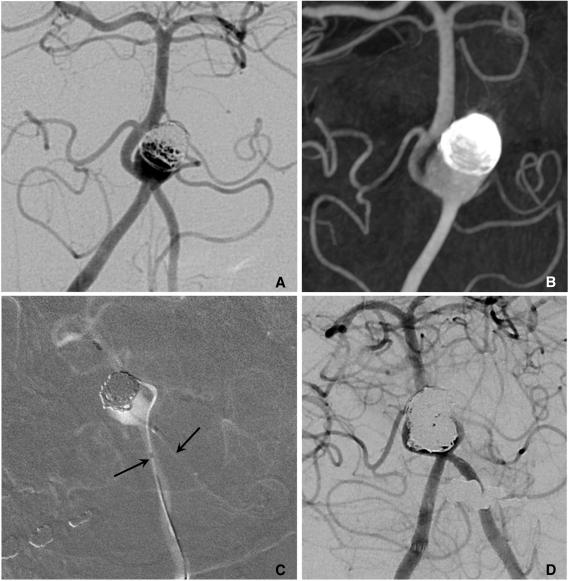

Stent application for the treatment of cerebral aneurysms.

Rapid and striking development in both the techniques and devices make it possible to treat most of cerebral aneurysms endovascularly. Stent has become one of the most important tools in treating difficult aneurysms not feasible for simple coiling. The physical features, the dimensions, and the functional characteristics of the stents show considerable differences. There are also several strategies and tips to treat difficult aneurysms by using stent and coiling. Nevertheless, they require much experience in clinical practice as well as knowledge of the stents to treat cerebral aneurysms safely and effectively. In this report, a brief review of properties of the currently available stents and strategies of their application is presented.

技术和设备的迅速显著发展使得大多数脑动脉瘤能够通过血管内治疗。支架已成为治疗难以单纯栓塞的复杂动脉瘤的最重要工具之一。不同支架的物理特性、尺寸和功能特点存在显著差异。使用支架辅助栓塞治疗复杂动脉瘤也有多种策略和技巧。然而,要安全有效地治疗脑动脉瘤,在临床实践中需要大量经验以及对支架的了解。本报告简要综述了目前可用支架的特性及其应用策略。